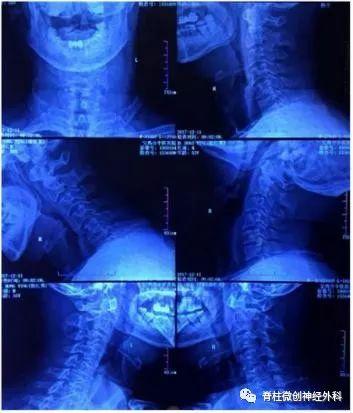

影像资料

从患者的影像资料可以看到一侧颈3-4椎间孔狭窄,患者出现的一侧神经根型症状和影像资料相符。临床上,一般建议此类患者做神经根的牵拉实验,如果实验呈阳性的话,基本可以诊断为神经根型颈椎病。

仔细看患者影像资料,过仰过伸位、中立位的检查都显示颈椎曲度还可以。临床上,有的患者颈椎曲度没有发生变化,但是神经根管处的钩椎关节有增生。对于此类患者,一般建议做颈椎的三维CT明确,多数时候可以看到钩椎关节神经根孔狭窄。